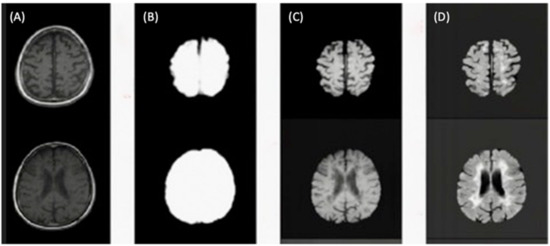

Figure 5 illustrates the skull-stripping process using the U-Net architecture for brain extraction described in step five.

Figure 5.

(A) Slices from original T1-w image. (B) Brain mask through skull-stripping using CNN. (C) Brain extraction in T1-w. (D) Brain extraction in FLAIR image.

Finally, to improve the signal intensity variability in MRIs caused by magnetic field inhomogeneities, we applied the image bias correction filter (N4ITK) in step six of the preprocessing after automatic brain extraction. Figure 6 illustrated an example of a slice with the application of the bias correction step. The brain extraction process and bias correction were applied to all the slices in the exam (each patient), and we were able to see the volumetric representation of the extracted brain (see Figure 7).

Figure 6.

(A) Rigidly registered image. (B) Skull-stripped image. (C) Bias correction filter. (D) Final image.